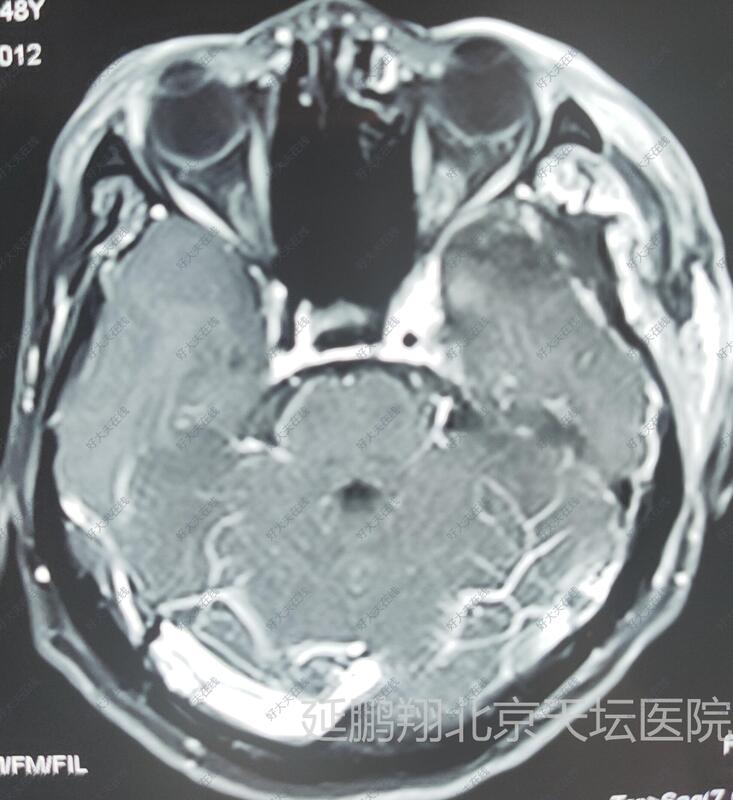

- 治疗后6天

术后病人恢复顺利,睡眠,进食,精神状态,行走均正常。常规复查核磁,显示肿瘤消失。